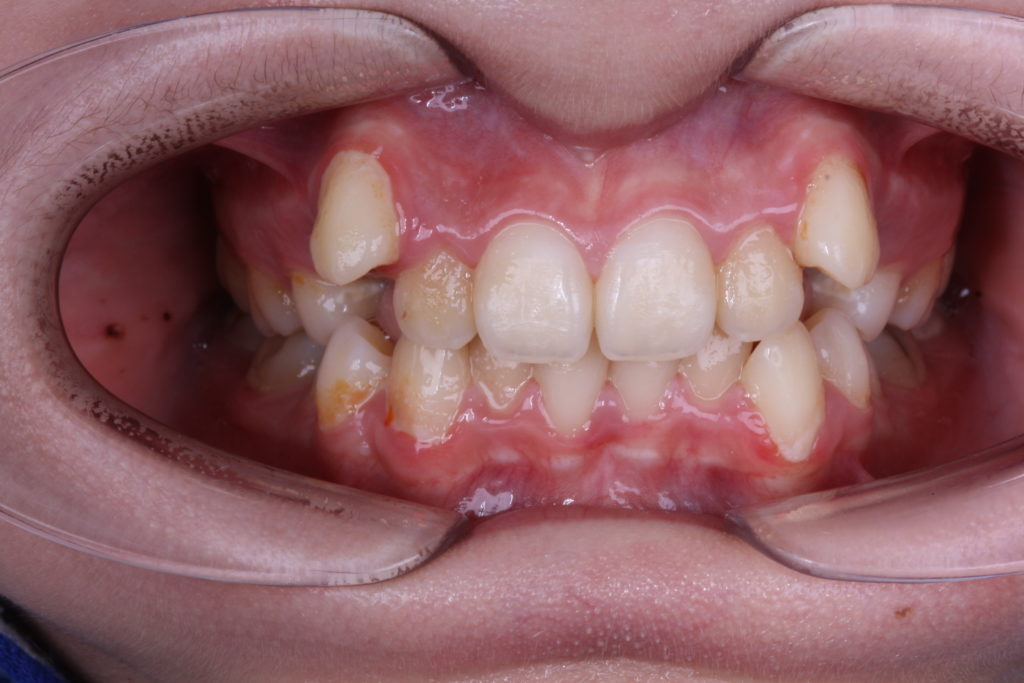

This patient came to my office at the age of 13 for ortho treatment. Her main concerns were crowding and high upper canines. Patient had severe crowding on upper jaw and had a full class II molar relationship. I decided to extract upper first premolars and start the treatment with fixed appliances (brackets).

I haven’t used any device for anchorage control, just the braces. I’ve included upper second molars for anchorage. I’ve started with early light elastics for high canines. I applied IPR for lower teeth to help with the crowding. Treatment lasted 12 months.